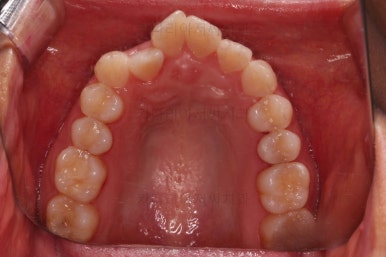

부산교정잘하는치과 초진 시 입안의 모습입ㄴ디ㅏ.

맞물림은 크게 나쁜 편은 아니었고요.

앞니 쪽이 위아래가 다 삐뚤고, 위에 작은 앞니 하나가 거꾸로 물리는 상태였습니다.

거꾸로 물리는 상황에서 특히 아래 앞니는 점점 잇몸이 꺼지는 증상이 생기면서 장기적인 치아의 수명에 영향을 주게 됩니다.